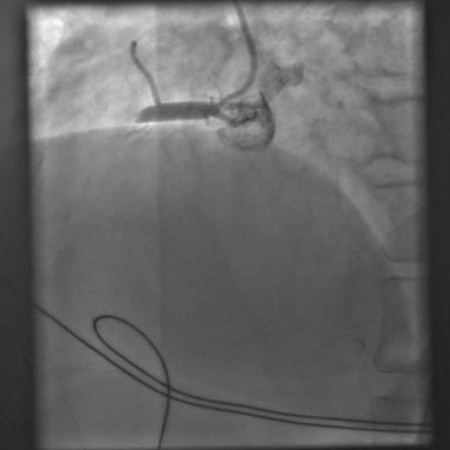

[Figure caption and citation for the preceding image starts]: Angiografia após a angioplastia com balão e colocação de stent mostrando uma artéria coronária direita abertaDo acervo pessoal do Dr. Mahi Ashwath; usado com permissão [Citation ends].